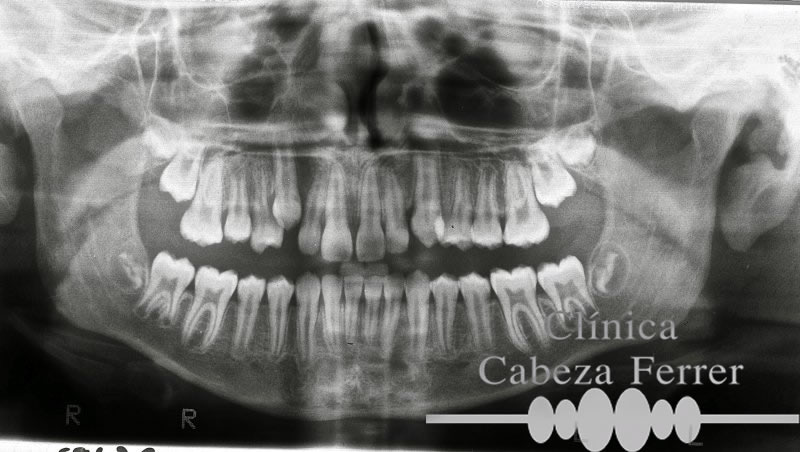

La exploración visual, radiográfica y la existencia de síntomas clínicos sirven de guía al profesional para decidir si es necesaria su extracción.

Existen muchas razones por las cuales los terceros molares necesitan extraerse, así cuando ocupan una posición anormal y erupcionan hacia la mejilla, hacia el paladar o hacia la lengua, también cuando hay una discrepancia con el tamaño del maxilar y mandíbula y ponen en peligro la estabilidad y alineamiento del resto de las piezas dentarias. Está también indicada su extracción cuando inflama permanentemente las encías, produce infecciones, dolor, quistes o altera la articulación de la mandíbula. En la inmensa mayoría de los casos las extracciones se realizan con anestesia local.

Generalmente entre los 16 y los 20 años de edad es el mejor momento para extraer las muelas del juicio, si es preciso, ya que a estas edades la corona de la muela está totalmente calcificada, pero las raíces no se encuentran totalmente desarrolladas y la cicatrización es rápida y sin complicaciones.